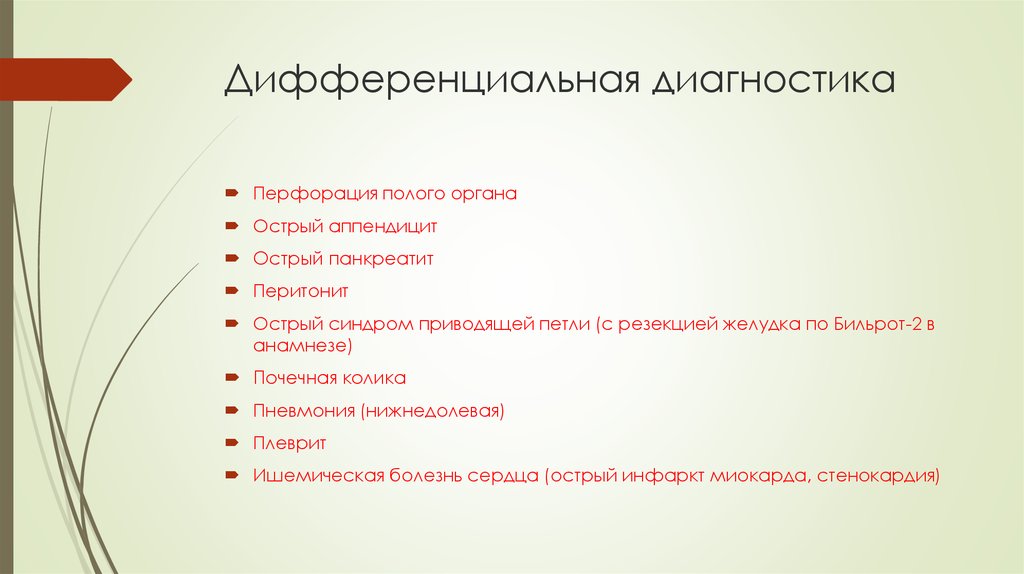

Дифференциальная диагностика заболеваний плевры